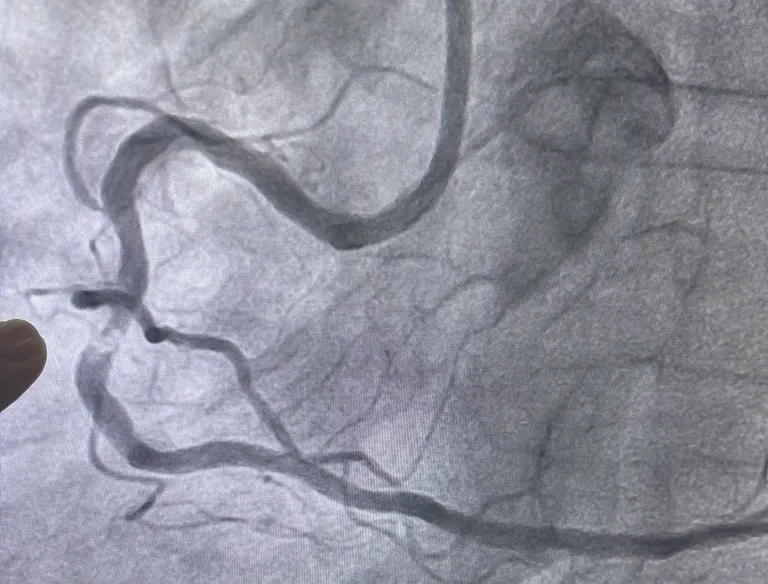

O procedimento foi conduzido pelos cardiologistas intervencionistas Thiago Lisboa e Glauco Gusmão, em um paciente que apresentava dor torácica e falta de ar intensas, com impacto direto na qualidade de vida. Exames de cateterismo cardíaco identificaram uma obstrução de 90% em uma artéria coronária, associada a uma placa extremamente calcificada — descrita pelos especialistas como um verdadeiro “bloco de cálcio”. Em situações como essa, técnicas convencionais de angioplastia tendem a ter limitações técnicas. Após a intervenção bem-sucedida, o paciente recebeu alta em menos de 24 horas.

De acordo com o cardiologista Thiago Lisboa, o sistema RotaPro é indicado especialmente para o tratamento de lesões coronarianas extensamente calcificadas. A tecnologia mantém a eficácia já consolidada da técnica tradicional, mas incorpora avanços importantes, como maior precisão e estabilidade durante o procedimento, redução do tempo de intervenção, menor exposição à radiação e potencial diminuição no uso de contraste — substância utilizada para visualizar as artérias.